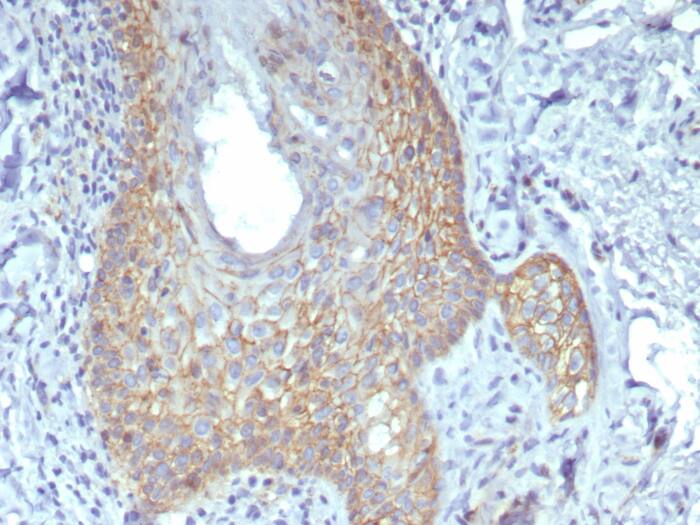

Formalin-fixed, paraffin-embedded human prostate stained with beta-Catenin antibody (rCTNNB1/8043) - Azide and BSA Free. HIER: Tris/EDTA, pH9.0, 45min. Secondary: HRP-polymer, 30min. DAB, 5min.